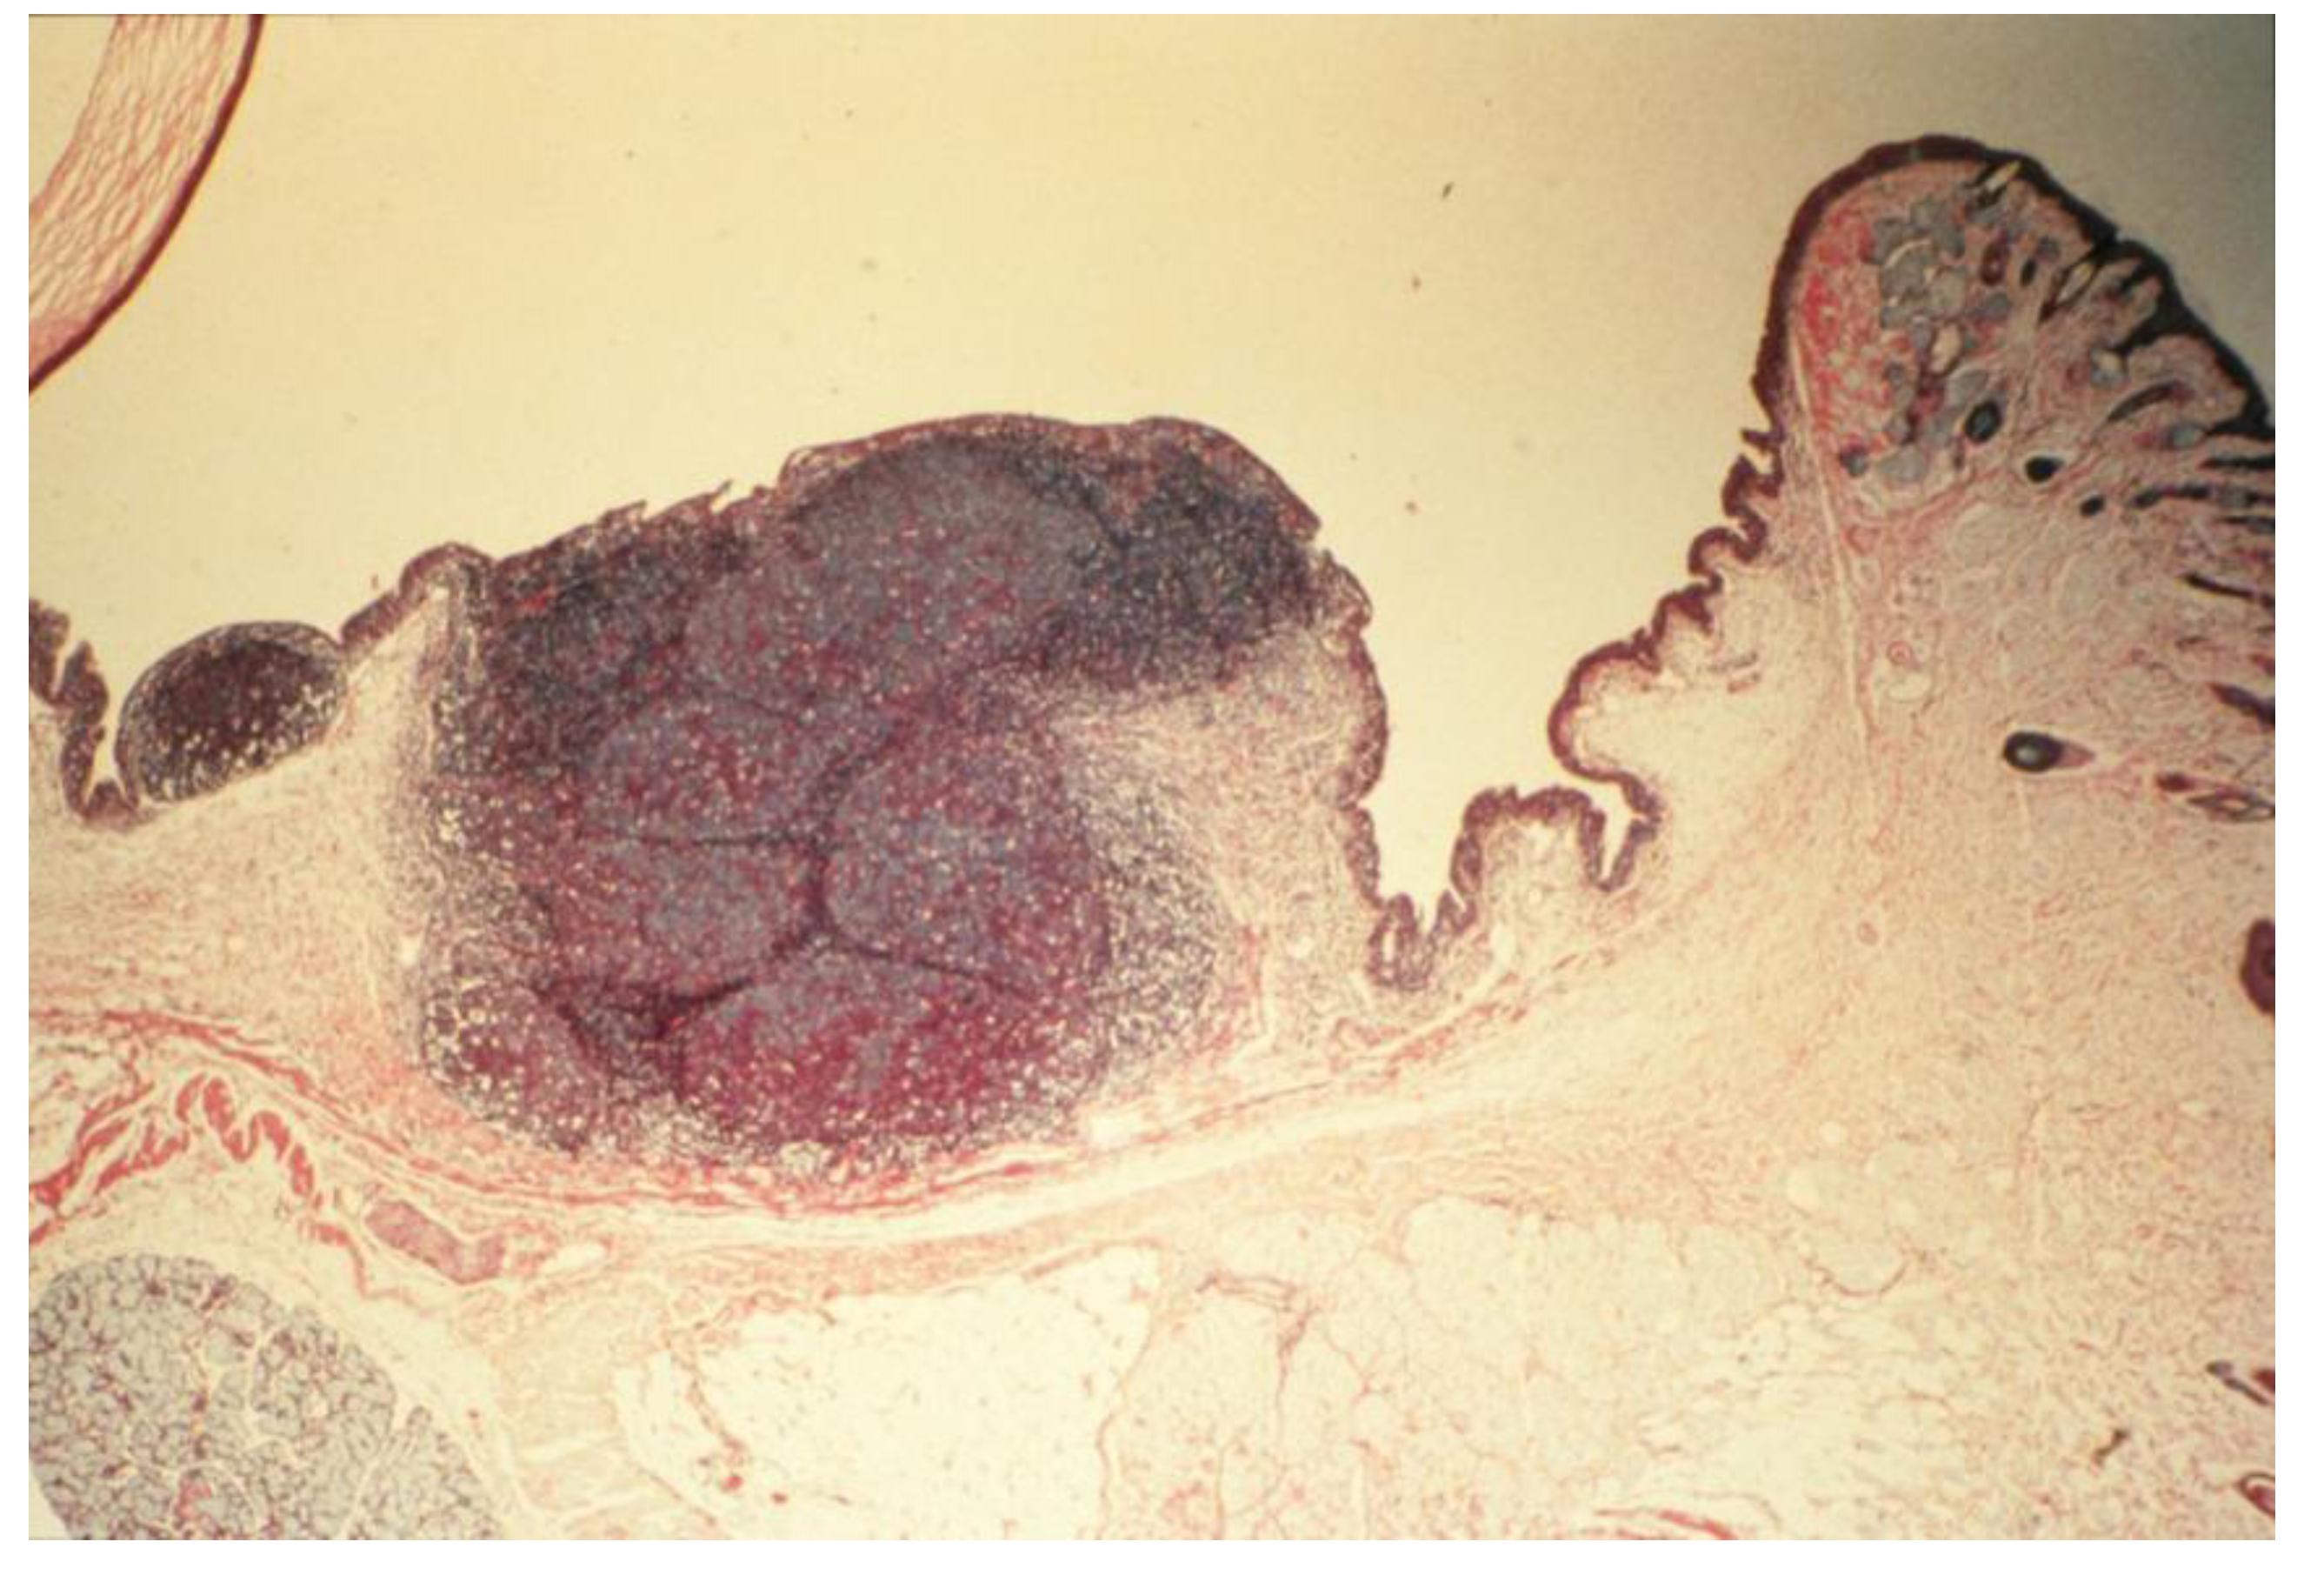

- Chronic-phase response, induction of tumorigenesis and angiogenesis: Occurring between 12 to 30 months of repeated tissue stimulation with FLOA. Findings included induction of tumor-like lesions in conjunctival tissues, angiogenesis, massive lymphoid hyperplasia, follicular formation with germinal centers, activated MFs, presence of histiocytes, loss of lymphocyte capsular membrane and extension of various sized B lymphocytes into surrounding epithelial tissues, increased swollen GCs, increased degranulated or partially granulated (“leaky”) MCs, involvement of lymphatic channels, extensive epithelial thickening (growth) and/or thinning (necrosis) often noted in the same tissue sections. Cross-sectional areas of massive hyperplastic lymphoid nodules from animals that were continuously challenged with antigen were at least five times larger than lymphoid tissues in normal-untreated animals (Figure 6) [3,36,37,39,45].Figure 5. Induction of down regulation in CALTs and eosinophil infiltration. Panel A; heavy eosinophils infiltration into GCs. Panel B; heavy eosinophils infiltration in conjunctival secretions from animals that were repeatedly challenged with topical application of FLOA and systemically immunized with A. Suum. Reproduced from Khatami et al. [35], @1984 American Medical Association, all rights reserved.Figure 5. Induction of down regulation in CALTs and eosinophil infiltration. Panel A; heavy eosinophils infiltration into GCs. Panel B; heavy eosinophils infiltration in conjunctival secretions from animals that were repeatedly challenged with topical application of FLOA and systemically immunized with A. Suum. Reproduced from Khatami et al. [35], @1984 American Medical Association, all rights reserved.

- Antibody profiles (humoral immunity, HI): Repeated stimulation of tissues and the induction of tumorigenesis produced significant increase in the expression of immunoglobulin isotypes (e.g., IgG1/IgG2 ratios) in culture media of massive hyperplastic CALTs, suggesting that frequent exposure to large dosage of antigen into substantia propria, or sub-epithelial tissues altered antibody profiles [3,37,88]. Indirect support for these observations came from the studies when guinea pigs were injected sub-conjunctivally with low dosage (or less frequent exposure) of nematode Onchocerca lienalis microfilaria; where no significant changes in biosynthesis of local IgG1 to IgG2 antibodies were observed in the cultures [3,90]. Others demonstrated diversities in the expression of cytokines and antibodies in B lymphocytes in humans and transgenic CCL2-deficient mouse models in the induction of inflammatory diseases or carcinogenesis [27,32,37]. The B lymphocytes in CCL2-deficient mice were shown to be unable to synthesize normal profiles of subclasses of antibodies, and continued synthesis of high levels of IgG2a and IgG2b, and low levels of IgG1, after immunization [3,27,28,32,37].Figure 6. Histopathologic section of eyelid of repeatedly topically immunized and challenged guinea pig showing massive hyperplasia of CALTs. Reproduced from Khatami et al. [36], @1989 American Medical Association, all rights reserved.Figure 6. Histopathologic section of eyelid of repeatedly topically immunized and challenged guinea pig showing massive hyperplasia of CALTs. Reproduced from Khatami et al. [36], @1989 American Medical Association, all rights reserved.